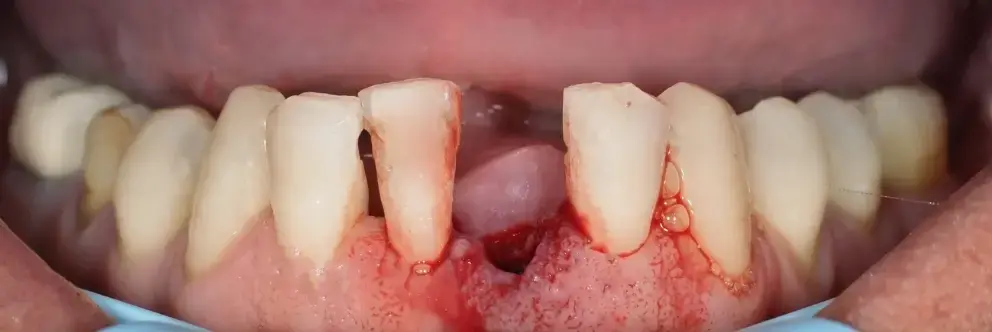

Bleeding Gums Are the First Warning Sign

Samuel’s story is just one of thousands proving that what starts with a drop of blood can end in loose teeth, shameful breath, and painful surgeries.